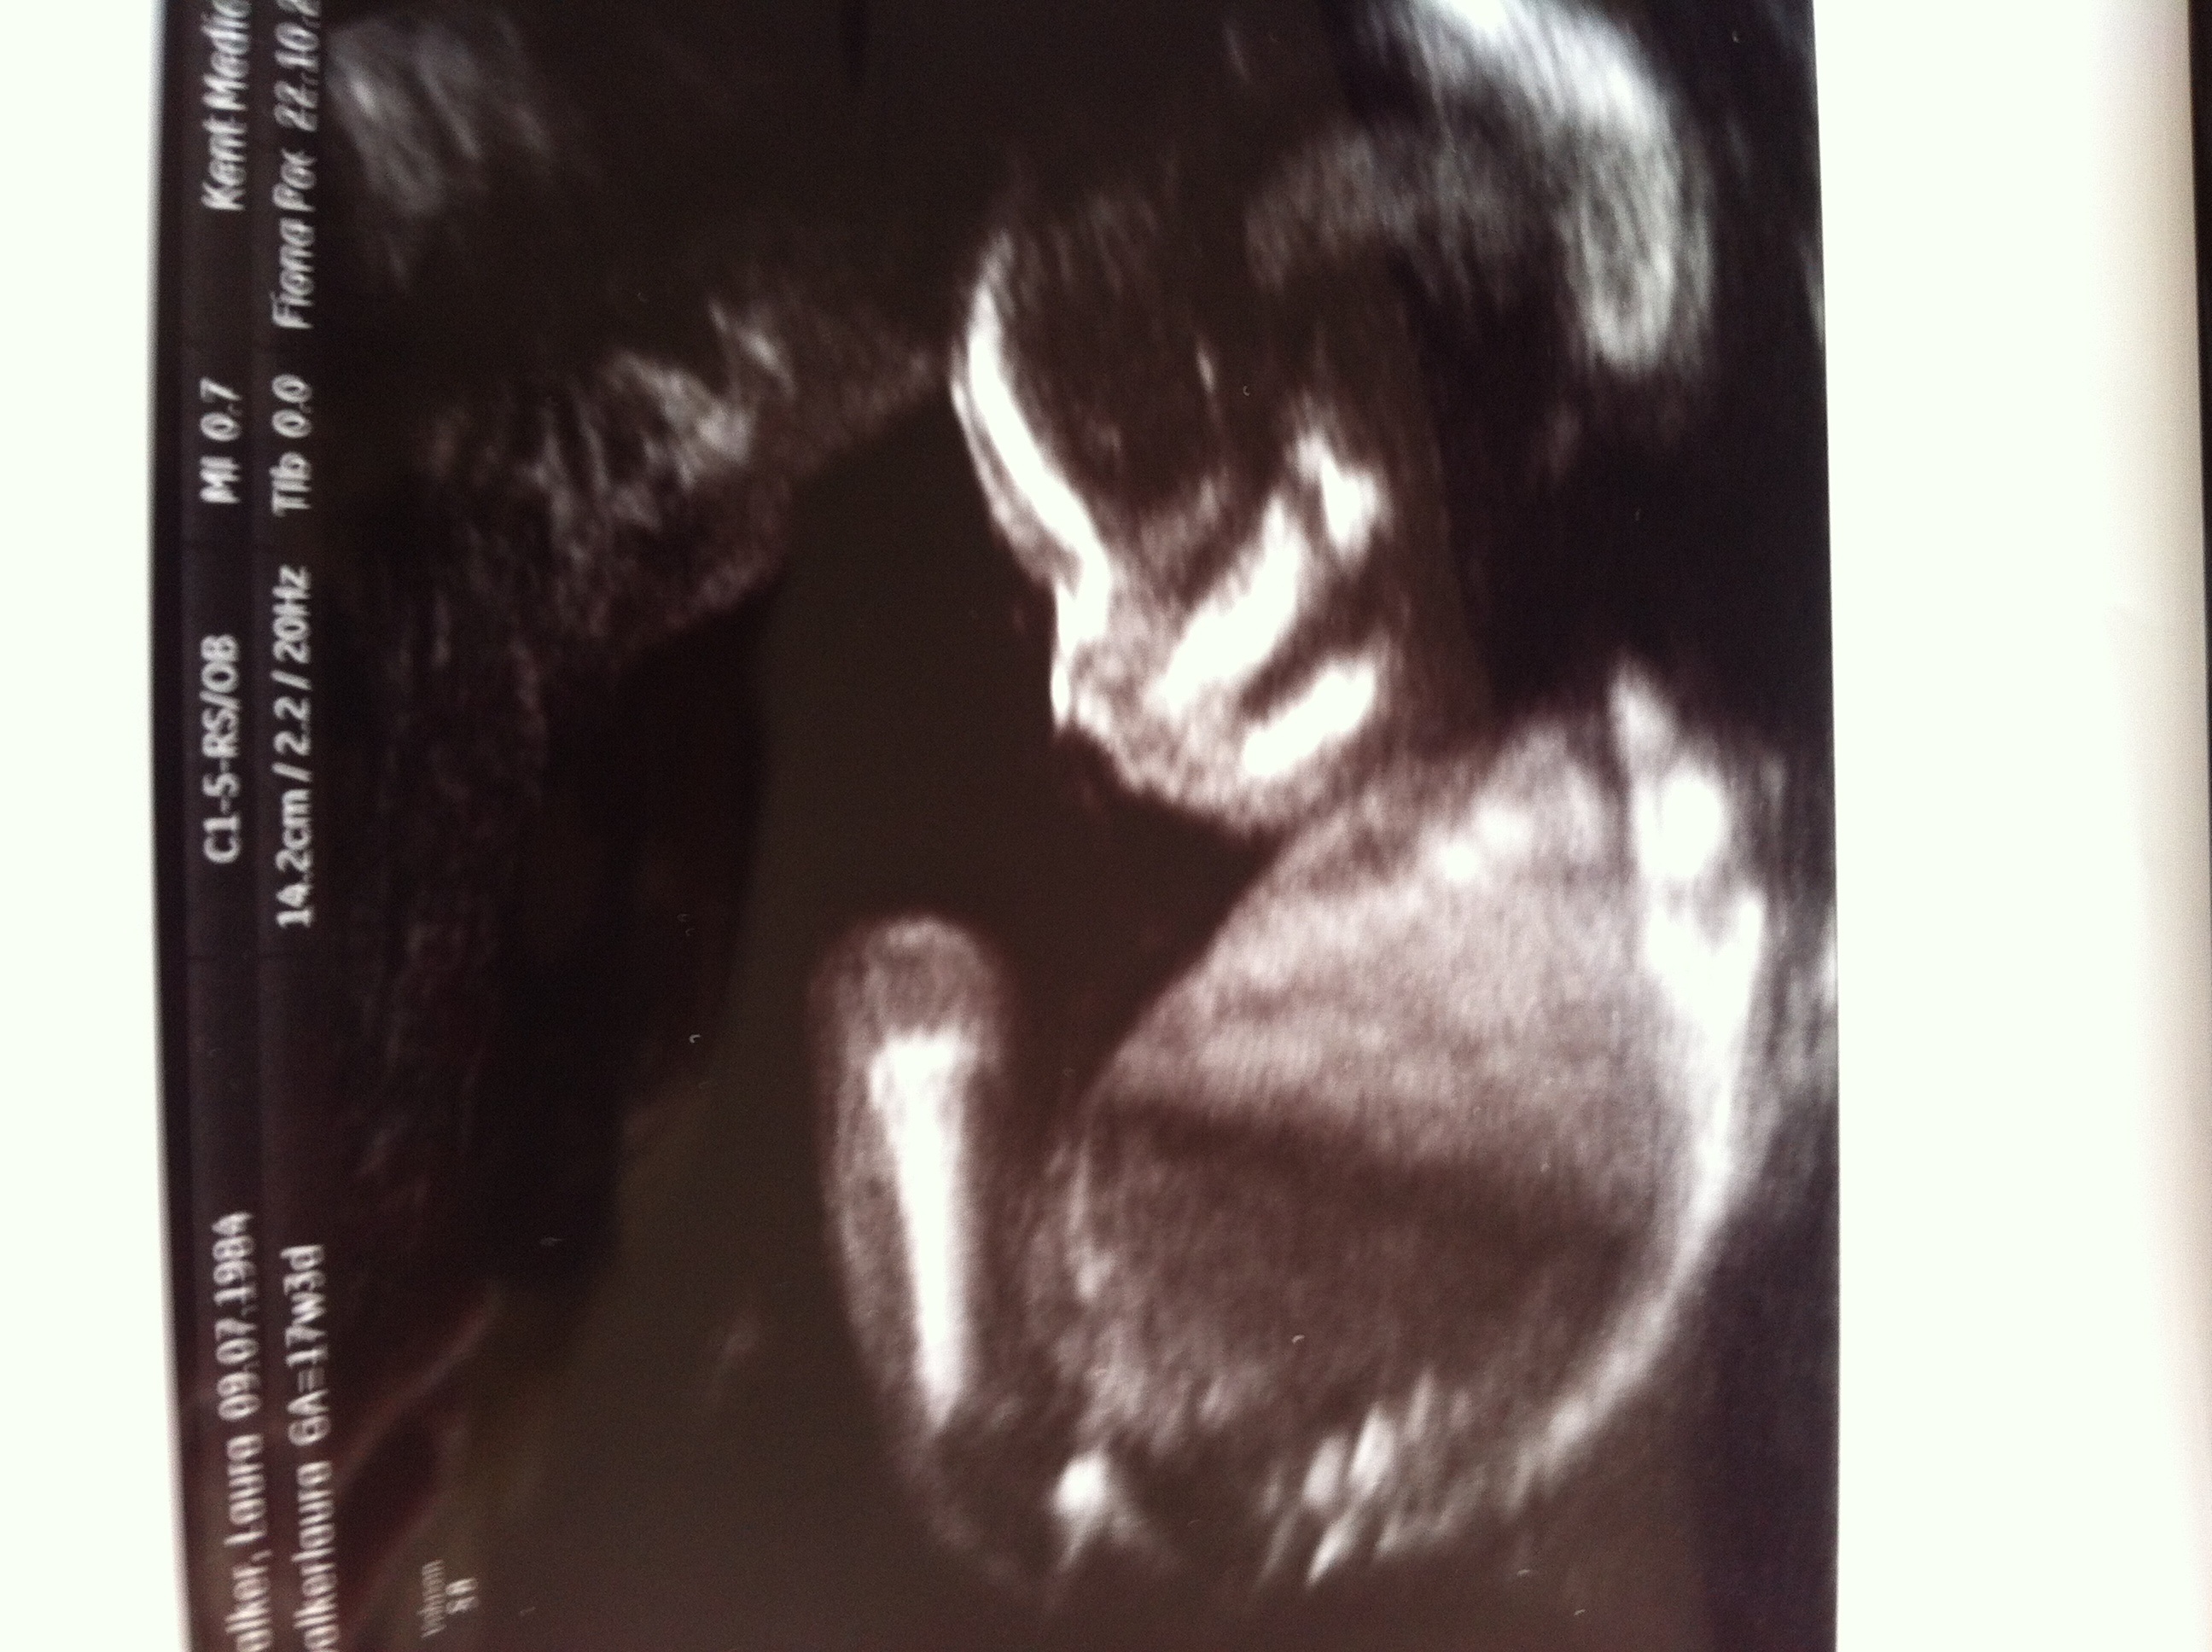

You had an ultrasound and the ultrasound sonographer told you that they're suspicious of a boy. Interesting to note, the doppler actually has higher levels of. Here's my experience with just that! However, compared to dating according to menstrual cycle, the ultrasound would be more accurate. The 12 weeks ultrasound examination can be done from 11 weeks 4 days to 13 weeks 6 days. Gender confirmed by harmony test! 12 weeks 5 days ultrasound/ gender reveal. Gender can be determined by ultrasound as early as 12 weeks in some cases. 12 weeks is little early but sometimes the gender can be seen. Ramzi theory explained by ultrasound technicians. Check out our 12 week ultrasound, where we find out the gender of our baby! My mom bawled her eyes out and you can hear. Is she spot on or should we wait until around 20 weeks to make sure?

After 12 weeks, its accuracy goes down. Gender detect by us after 33 weeks in position of placenta posterior upper segementt grade ii maturity.heart beat 149.in 26 week us report. Check out my designer online children's. Had our 12 week ultrasound today!! Interesting to note, the doppler actually has higher levels of. 11 week scan any gender guesses. This question doesn't have a straight forward answer. Gender confirmed by harmony test! 12 week ultrasound for gender reveal. A 2016 study looked at the accuracy of such tests. See more ideas about ultrasound gender, ultrasound, gender prediction. You had an ultrasound and the ultrasound sonographer told you that they're suspicious of a boy. The 12 weeks ultrasound examination can be done from 11 weeks 4 days to 13 weeks 6 days.

It really depends on the technician, the quality of the sonogram machine and. Ramzi theory explained by ultrasound technicians. 12 weeks 5 days ultrasound/ gender reveal. Patient who presents to the hospital in labor close to term without any prenatal care or ultrasound can have a dating of pregnancy that is. My mom bawled her eyes out and you can hear. 12 week ultrasound gender ultrasound gender prediction ultrasound tech ultrasound pictures boy or can an ultrasound reveal gender at 12 weeks? For performing gender reveal ultrasound as the baby is usually more than 13 weeks the accuracy of the gender reveal ultrasound will be reduced and the clarity of images in 3d ultrasound will be less. Whats the accuracy of sonographic determination of fetal gender study.

Most people are not that lucky. Whats the accuracy of sonographic determination of fetal gender study. Gender detect by us after 33 weeks in position of placenta posterior upper segementt grade ii maturity.heart beat 149.in 26 week us report. At twelve week on ultrasound, the sonographer measures the fetus' crown rump length (crl). 11 week scan any gender guesses. Ultrasound imaging performed in the 11th and 12th weeks of pregnancy for fetal gender identification identified the fetus either as a girl, a boy, or as a gender not assigned. frequency, sensitivity, specificity, positive and negative predictive values, and accuracy of the gender identification was. Would love some guesses on what it is :)&nb. This question doesn't have a straight forward answer. 19 week gender scan accuracy. Patient who presents to the hospital in labor close to term without any prenatal care or ultrasound can have a dating of pregnancy that is. Male gender may already be reliably determined when crl ≥ 55 mm (gestational age ≥ 12+0). I'm not sure now where it is! Is she spot on or should we wait until around 20 weeks to make sure?